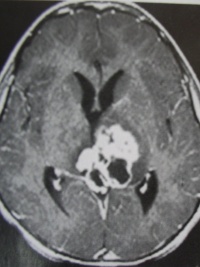

生殖细胞瘤水平切面图像

1.CT表现:

①肿瘤最常见于松果体区,位于鞍上区肿块常累及漏斗;

②CT平扫多呈等密度或稍高密度肿块,无出血、坏死及囊性变,可分叶,但境界清楚;瘤体本身钙化少见,典型松果体区生殖细胞瘤常见肿瘤包埋松果体钙化灶

③增强扫描呈中等至明显的均匀强化。

室管膜下转移可表现为沿脑室壁线状或条片状强化,沿脑脊液向蛛网膜下腔播散表现为脑表面、脑池的线状或结节状强化。